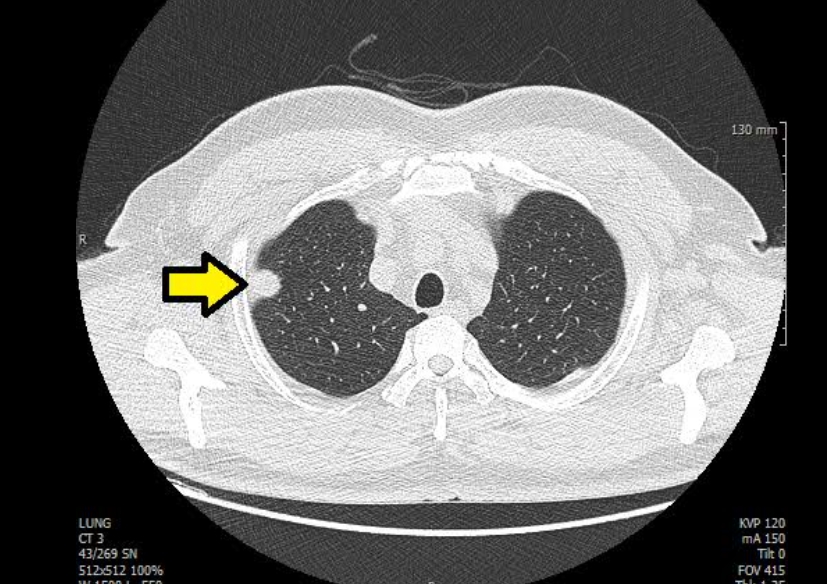

흉부 엑스레이 결절음영

결절음영이란 말은 엑스레이에서 ‘혹처럼 보이는 부분’을 뜻해요. 작게 하얗게 보이는 점, 혹은 둥근 모양의 그림자가 결절음영입니다. 이게 보이면 대부분은 오래된 염증, 흉터, 석회화(염증이 낫고 남은 흔적)일 때가 많아요.

하지만 간혹 크기가 크거나 모양이 울퉁불퉁한 경우엔 폐암 같은 질환을 의심하기도 합니다. 그래서 보통은 “추적 관찰”을 권해요. 6개월 또는 1년 뒤 다시 찍어서 변화가 없는지 보는 거죠. 제 지인 중 한 분도 건강검진에서 결절음영이 나와서 놀랐지만, 재검 때는 흔적만 남고 없어졌어요. 그때 이후로는 주기적으로 검사받는 걸 잊지 않으신다고 하더라구요.